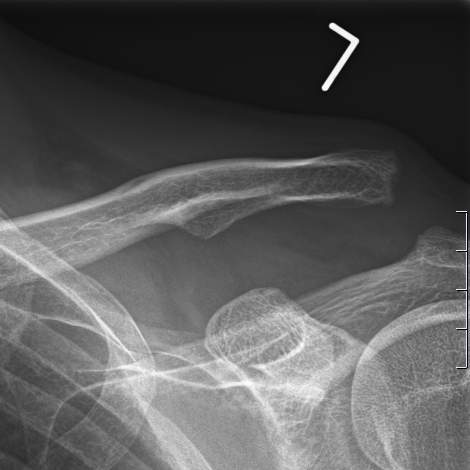

Akute oder chronische Schultereckgelenkssprengungen treten häufig nach Stürzen auf. Hier ist bei hochgradigen Verletzungen die operative Stabilisierung notwendig. Während die akuten Verletzungen minimal invasiv versorgt werden können, ist bei chronischen Verletzungen häufig die Verstärkung mit körpereigener Sehne (wie bei der Kreuzband-OP) notwendig.